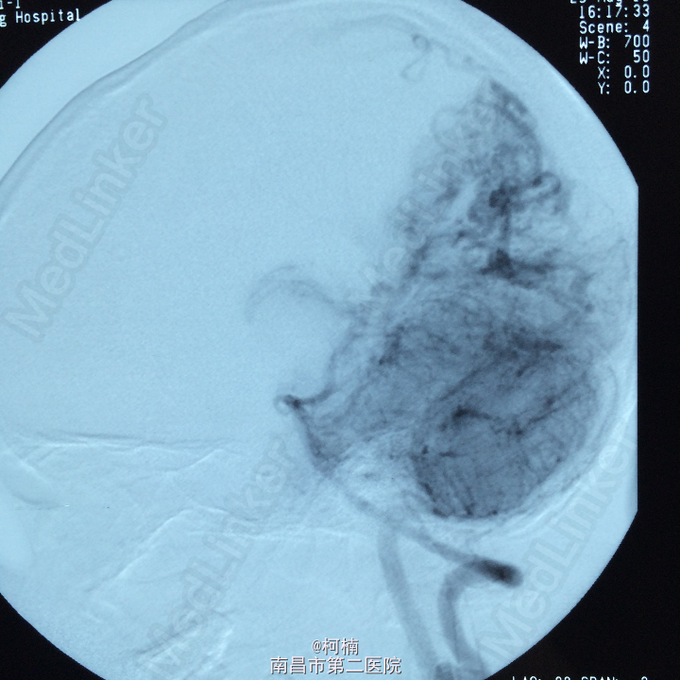

诊断:脑动静脉畸形 处理:予急诊行DSA检查,提示脑动静脉畸形,予行血管内栓栓塞治疗